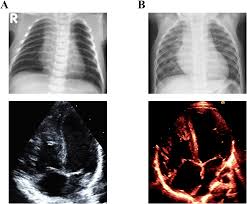

日本小児循環器学会雑誌